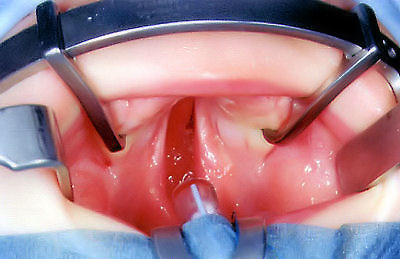

Lippen-Kieferspalte linksseitig

Mundvorhofstörung (Vomerstörung)

mittig sichtbar

Komplettspaltbildung

Lippen-Kiefer-Gaumen-Segel-Nasen(Spalt)-Fehlbildung

Kieferspalte angedeutet linksseitig erkennbar

Gaumenspalte durchgängig über harten-weichen Gaumen bis

zum Segelgaumen

Segel gleichfalls gespalten